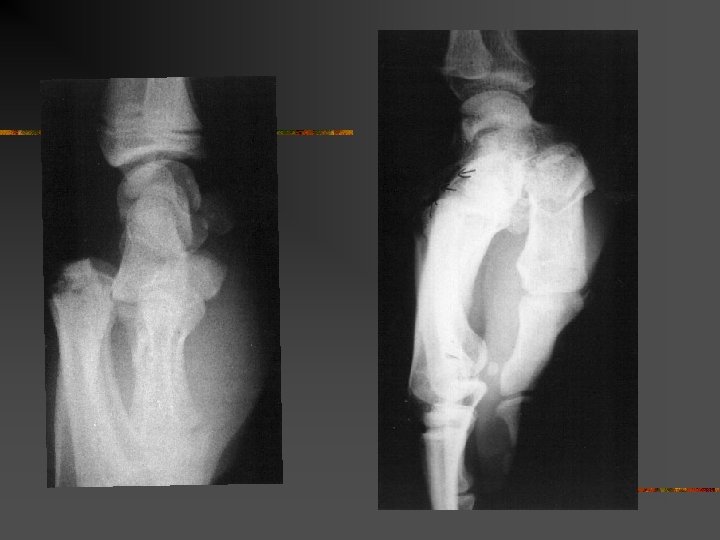

Homme 16 ans. Traumatisme des deux mains par bombe artisanale

Homme 16 ans. traumatisme des deux mains par bombe artisanale amputation à gauche et lambeau IOP à droite

Homme de 61 ans. Traumatisme index droit par pétard à taupe. Dévascularisation. Revascularisation par pontage veineux